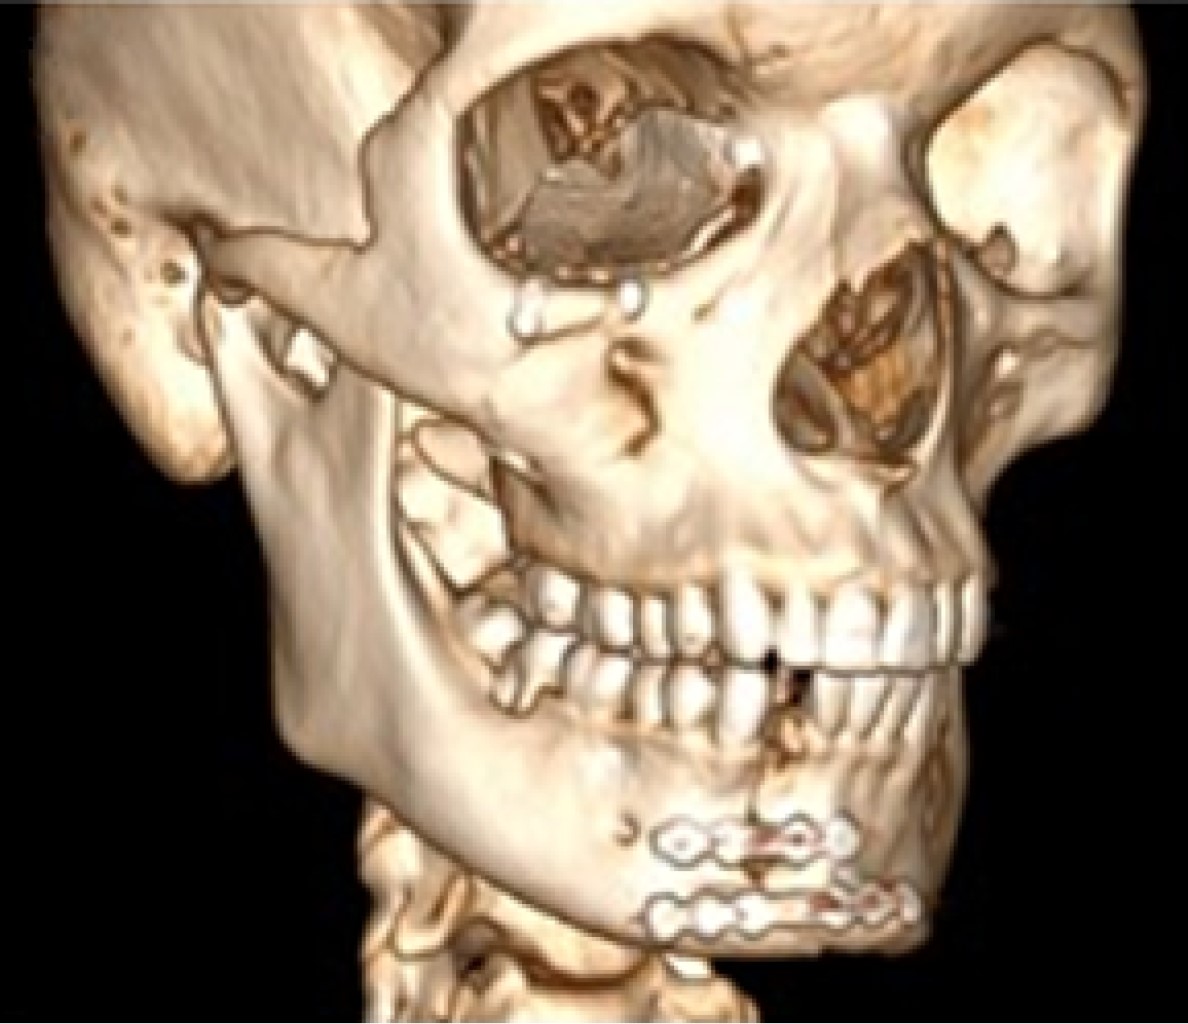

Paciente varón de 28 años que sufrió una caída de aproximadamente tres metros debido a una descarga eléctrica. Fue atendido por el servicio de Cirugía Oral y Maxilofacial y Traumatología del Hospital Santa Casa de Araraquara servicio de urgencias de primera atención/São Paulo. El examen físico extraoral mostró hueso frontal con escalón óseo en el techo de la órbita en el lado izquierdo, pupilas isocóricas y fotorreactivas, movimientos oculares libres, ausencia de diplopía monocular y binocular, y proyección alterada del cigomático derecho.

Una tomografía computarizada de la cara mostró una fractura de tipo Le Fort I del suelo, de la pared medial y del techo orbitario bilateral, fractura del cigomático derecho y de la pared anterior del hueso frontal.

Bajo anestesia general, el paciente fue intervenido cinco días después del traumatismo para la reducción y fijación de las fracturas realizando un acceso bicoronal (Figura 1), infraciliar bilateral, sutura frontozigomática del lado izquierdo y acceso intraoral de Caldwell-Luc en fondo del saco superior del lado derecho. Las fracturas orbitarias bilaterales se reconstruyeron con malla de titanio en el suelo, la pared medial y el techo orbitario; todas las fracturas se fijaron con placas y tornillos del sistema de 1.5 mm; se realizó una prueba de ducción forzada con pinzas Adson y la movilidad del globo terráqueo fue satisfactoria (Figura 2).

En la tomografía computarizada postoperatoria de la cara se puede observar la reconstrucción de las fracturas del seno frontal, del techo, de la pared medial y del suelo orbitario y sus respectivas fijaciones (Figuras 3 y 4).

Paciente en seguimiento ambulatorio durante tres años sin quejas, se mantuvo clínicamente sin evidencia de infección ni complicación grave como diplopía y enoftalmia, buena proyección del cigomático derecho, sin cambios oculares ni intercurrencias durante este periodo postoperatorio (Figura 4).